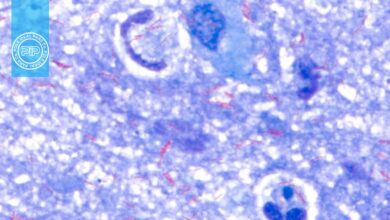

نتایج و تفسیر رنگآمیزی تریکروم ویتلی

نتایج رنگ آمیزی تریکروم ویتلی به صورت زیر خواهد بود:

- مشاهده پروتوزوآها: تروفوزوئیتها و کیستهای پروتوزوآ باید زیر میکروسکوپ بررسی شوند.

- رنگآمیزی سیتوپلاسم تروفوزوئیتها: معمولاً آبی-سبز یا بنفش روشن دیده میشود.

- رنگآمیزی کیستها:کیستها رنگ بنفشتر دارند.

- مشاهده سلولهای انسانی و مخمر: سلولهایی مانند گلبولهای قرمز (RBCs)، پلیمورفونوکلئرها (PMNs)، ماکروفاژها و همچنین مخمرها میتوانند شناسایی شده و به رنگ قرمز دیده شوند.

- هستهها و اجسام داخل سلولی: هستهها و inclusion bodies نیزرنگ قرمز با تهرنگ بنفش به خود میگیرند.

- پسزمینه : پسزمینه رنگ سبز دارد و این باعث کنتراست بالا با پروتوزوآها میشود.

- گلیکوژن: مولکولهای گلیکوژن توسط حلالهای رنگ حل میشوند و به صورت شفاف و بدون رنگآمیزی دیده میشوند، درست مانند خود ارگانیسم.